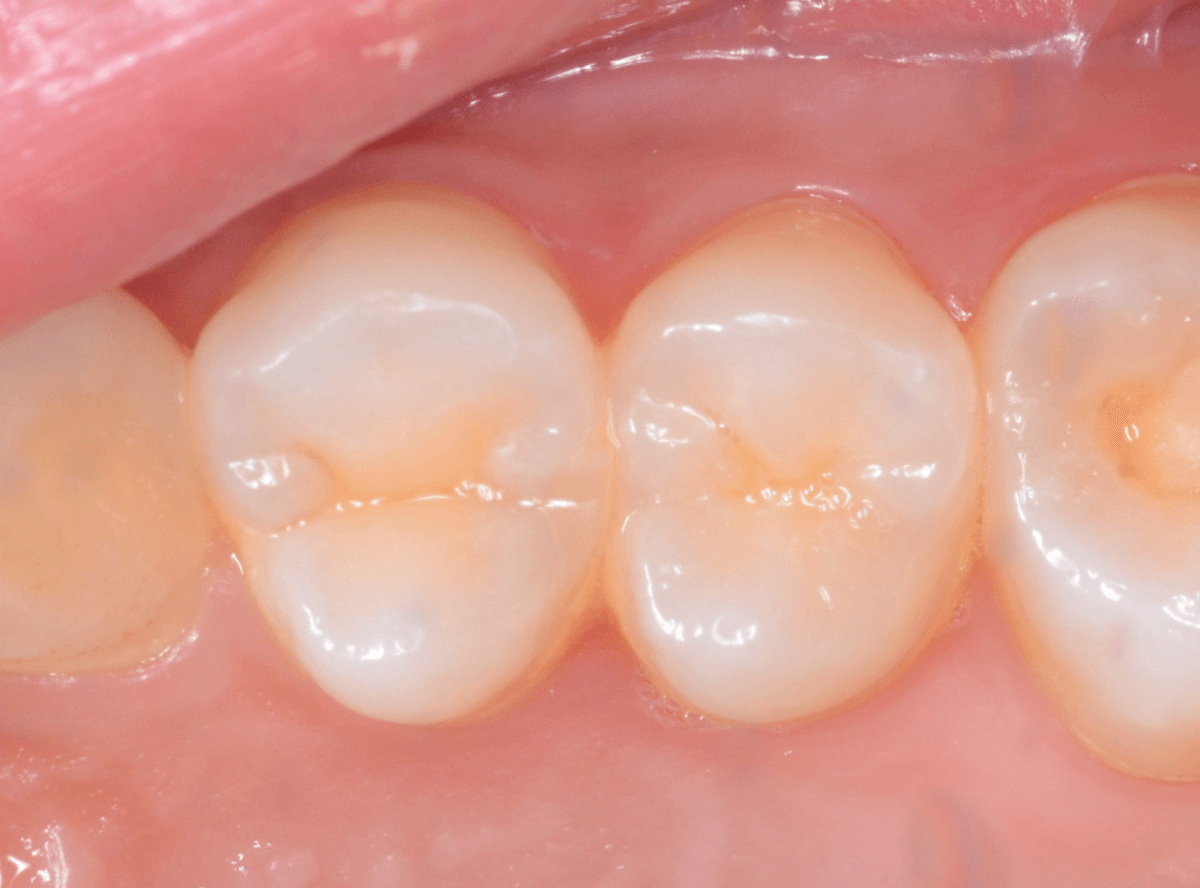

お口の中を拝見すると、数か所アヤシイ箇所がありました。その中の一つです。

この写真では、問題なさそうですね。